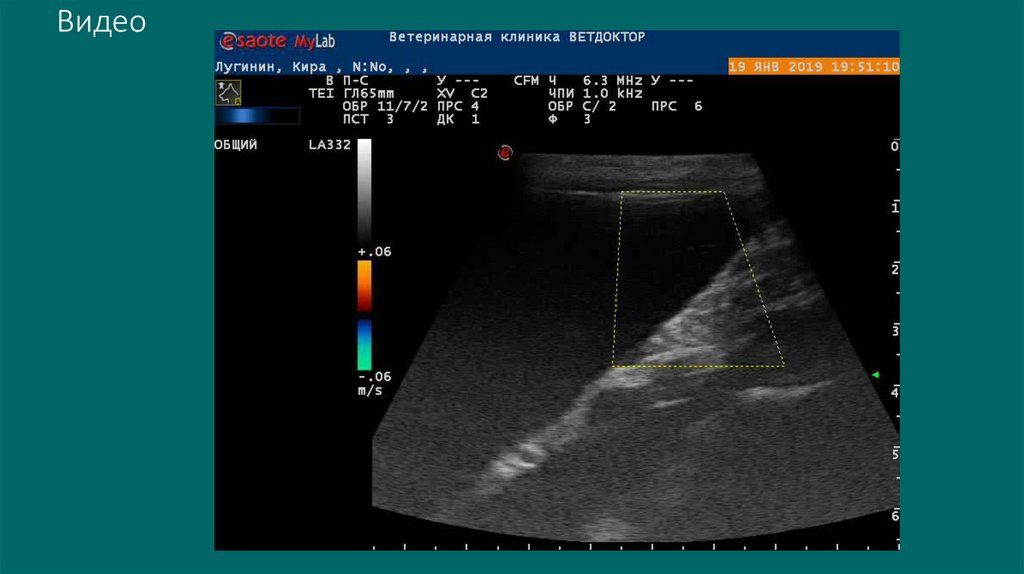

Видео

Гидронефроз это не всегда нефроэктомия